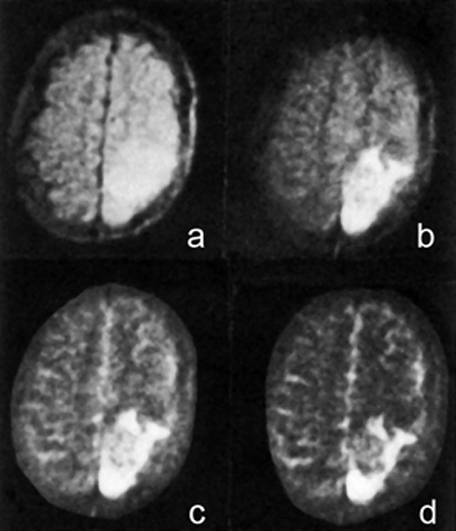

Figura 20-43:

Imágenes de espín-eco de 1984 de un tumor cerebral recurrente tomadas en un sistema de 0,14 Tesla; TEs (a-d) entre 20 y 300 ms.

Los tiempos de eco largos en secuencias CPMG multieco supusieron un gran avance en la primera mitad de la década de 1980. Pasaron algunos años hasta que las imágenes ponderadas en T2 fueron generalmente aceptadas, sobre todo porque muchas empresas afirmaban que los TE largos no eran posibles ni necesarios.

Las imágenes se realizaron cinco años antes de la introducción de los agentes de contraste basados en Gd; el tumor se puede delinear mejor en la imagen (d) con un TE de 300 ms.

Ilustración de: Rinck PA, Bydder GM, y Harms SE. Imaginería por resonancia magnética del cerebro. Publicado en la primera edición de este libro de texto en 1985.